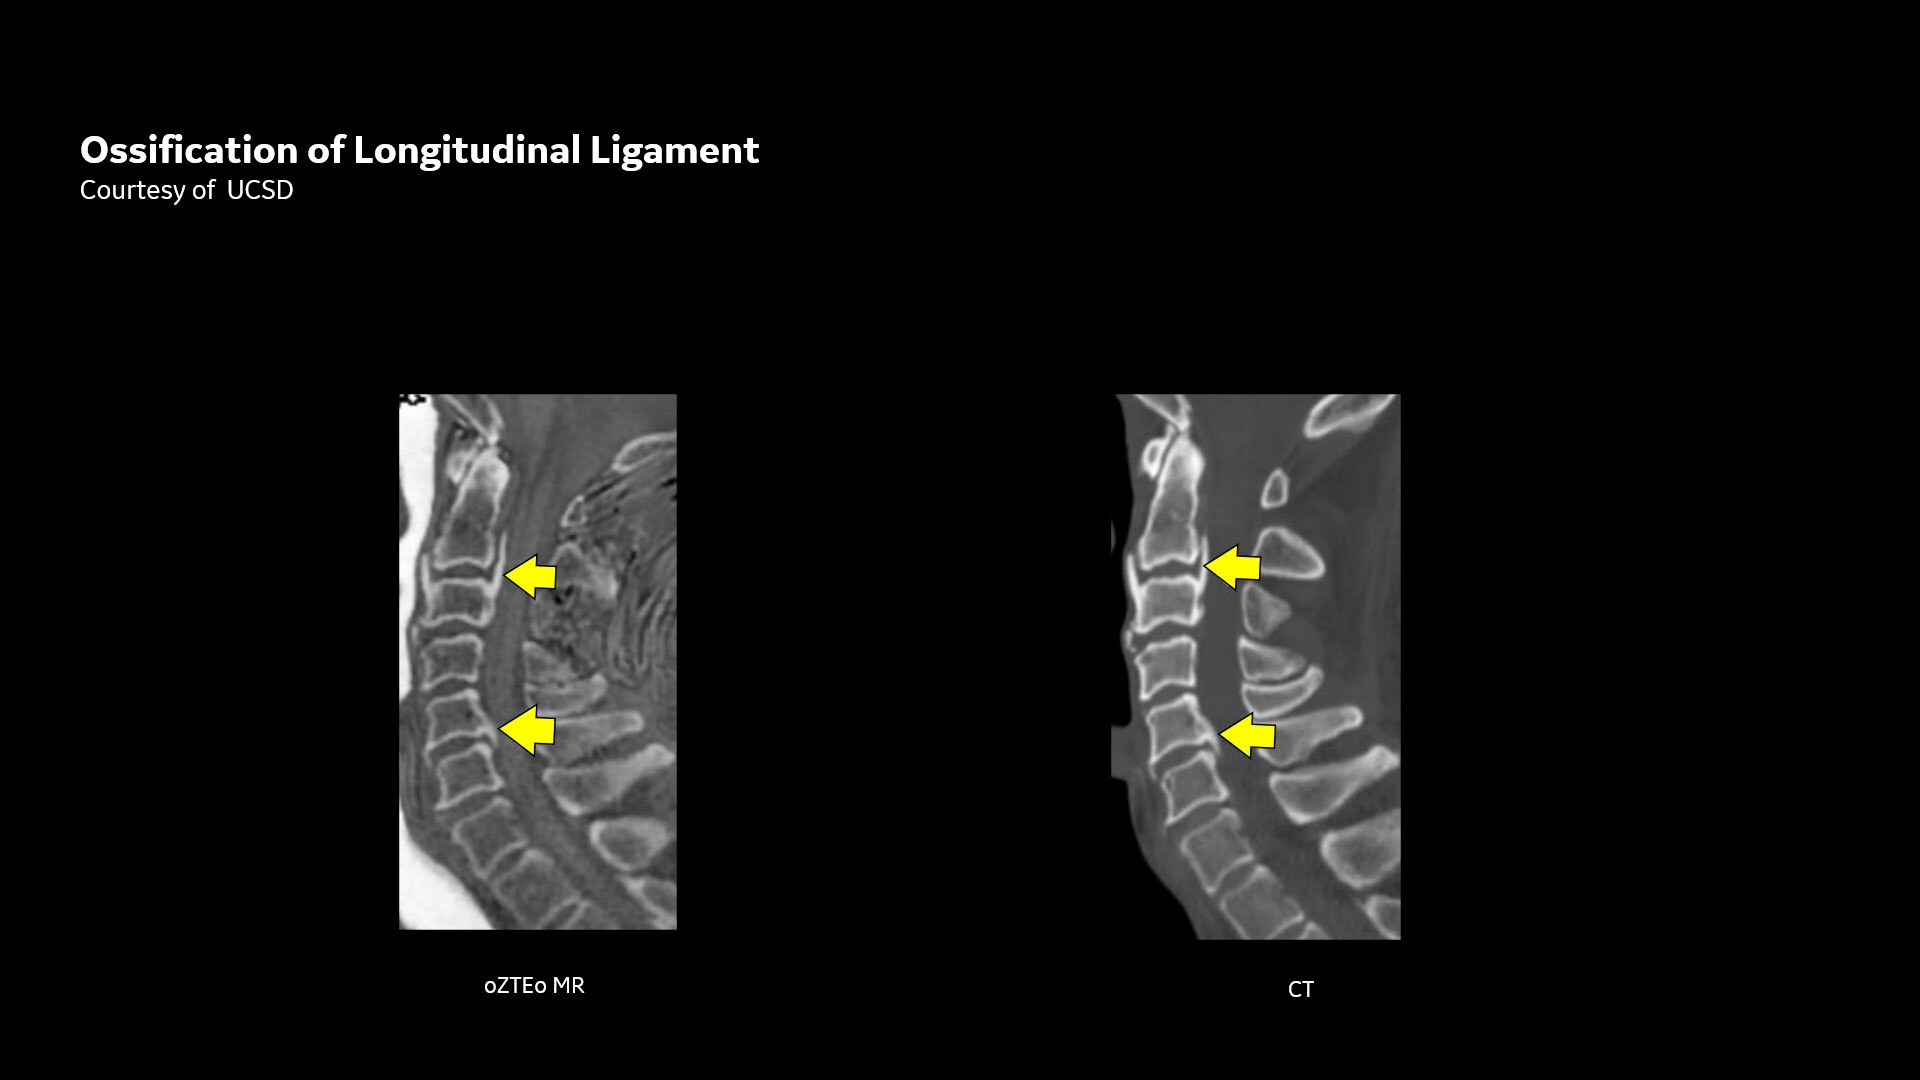

Powerful bone imaging for all anatomies

Available for all anatomies without ionizing radiation, oZTEo delivers images of bone morphology, calcification, ossification and fractures. oZTEo complements conventional MR soft tissue exams with perfect co-registration and provides 3D isotropic imaging using a radial ZTE acquisition, with inherent motion insensitivity. Use oZTEo with Volume Illumination for realistic 3D rendering.

CT-like image contrast without ionizing radiation

MR bone imaging provides a CT-like image contrast without ionizing radiation, making it an attractive alternative for pediatric and pregnant patients where ionizing radiation is a concern. In addition, it provides a welcome alternative when longitudinal CTs are required, particularly when low-dose CT systems are unavailable.